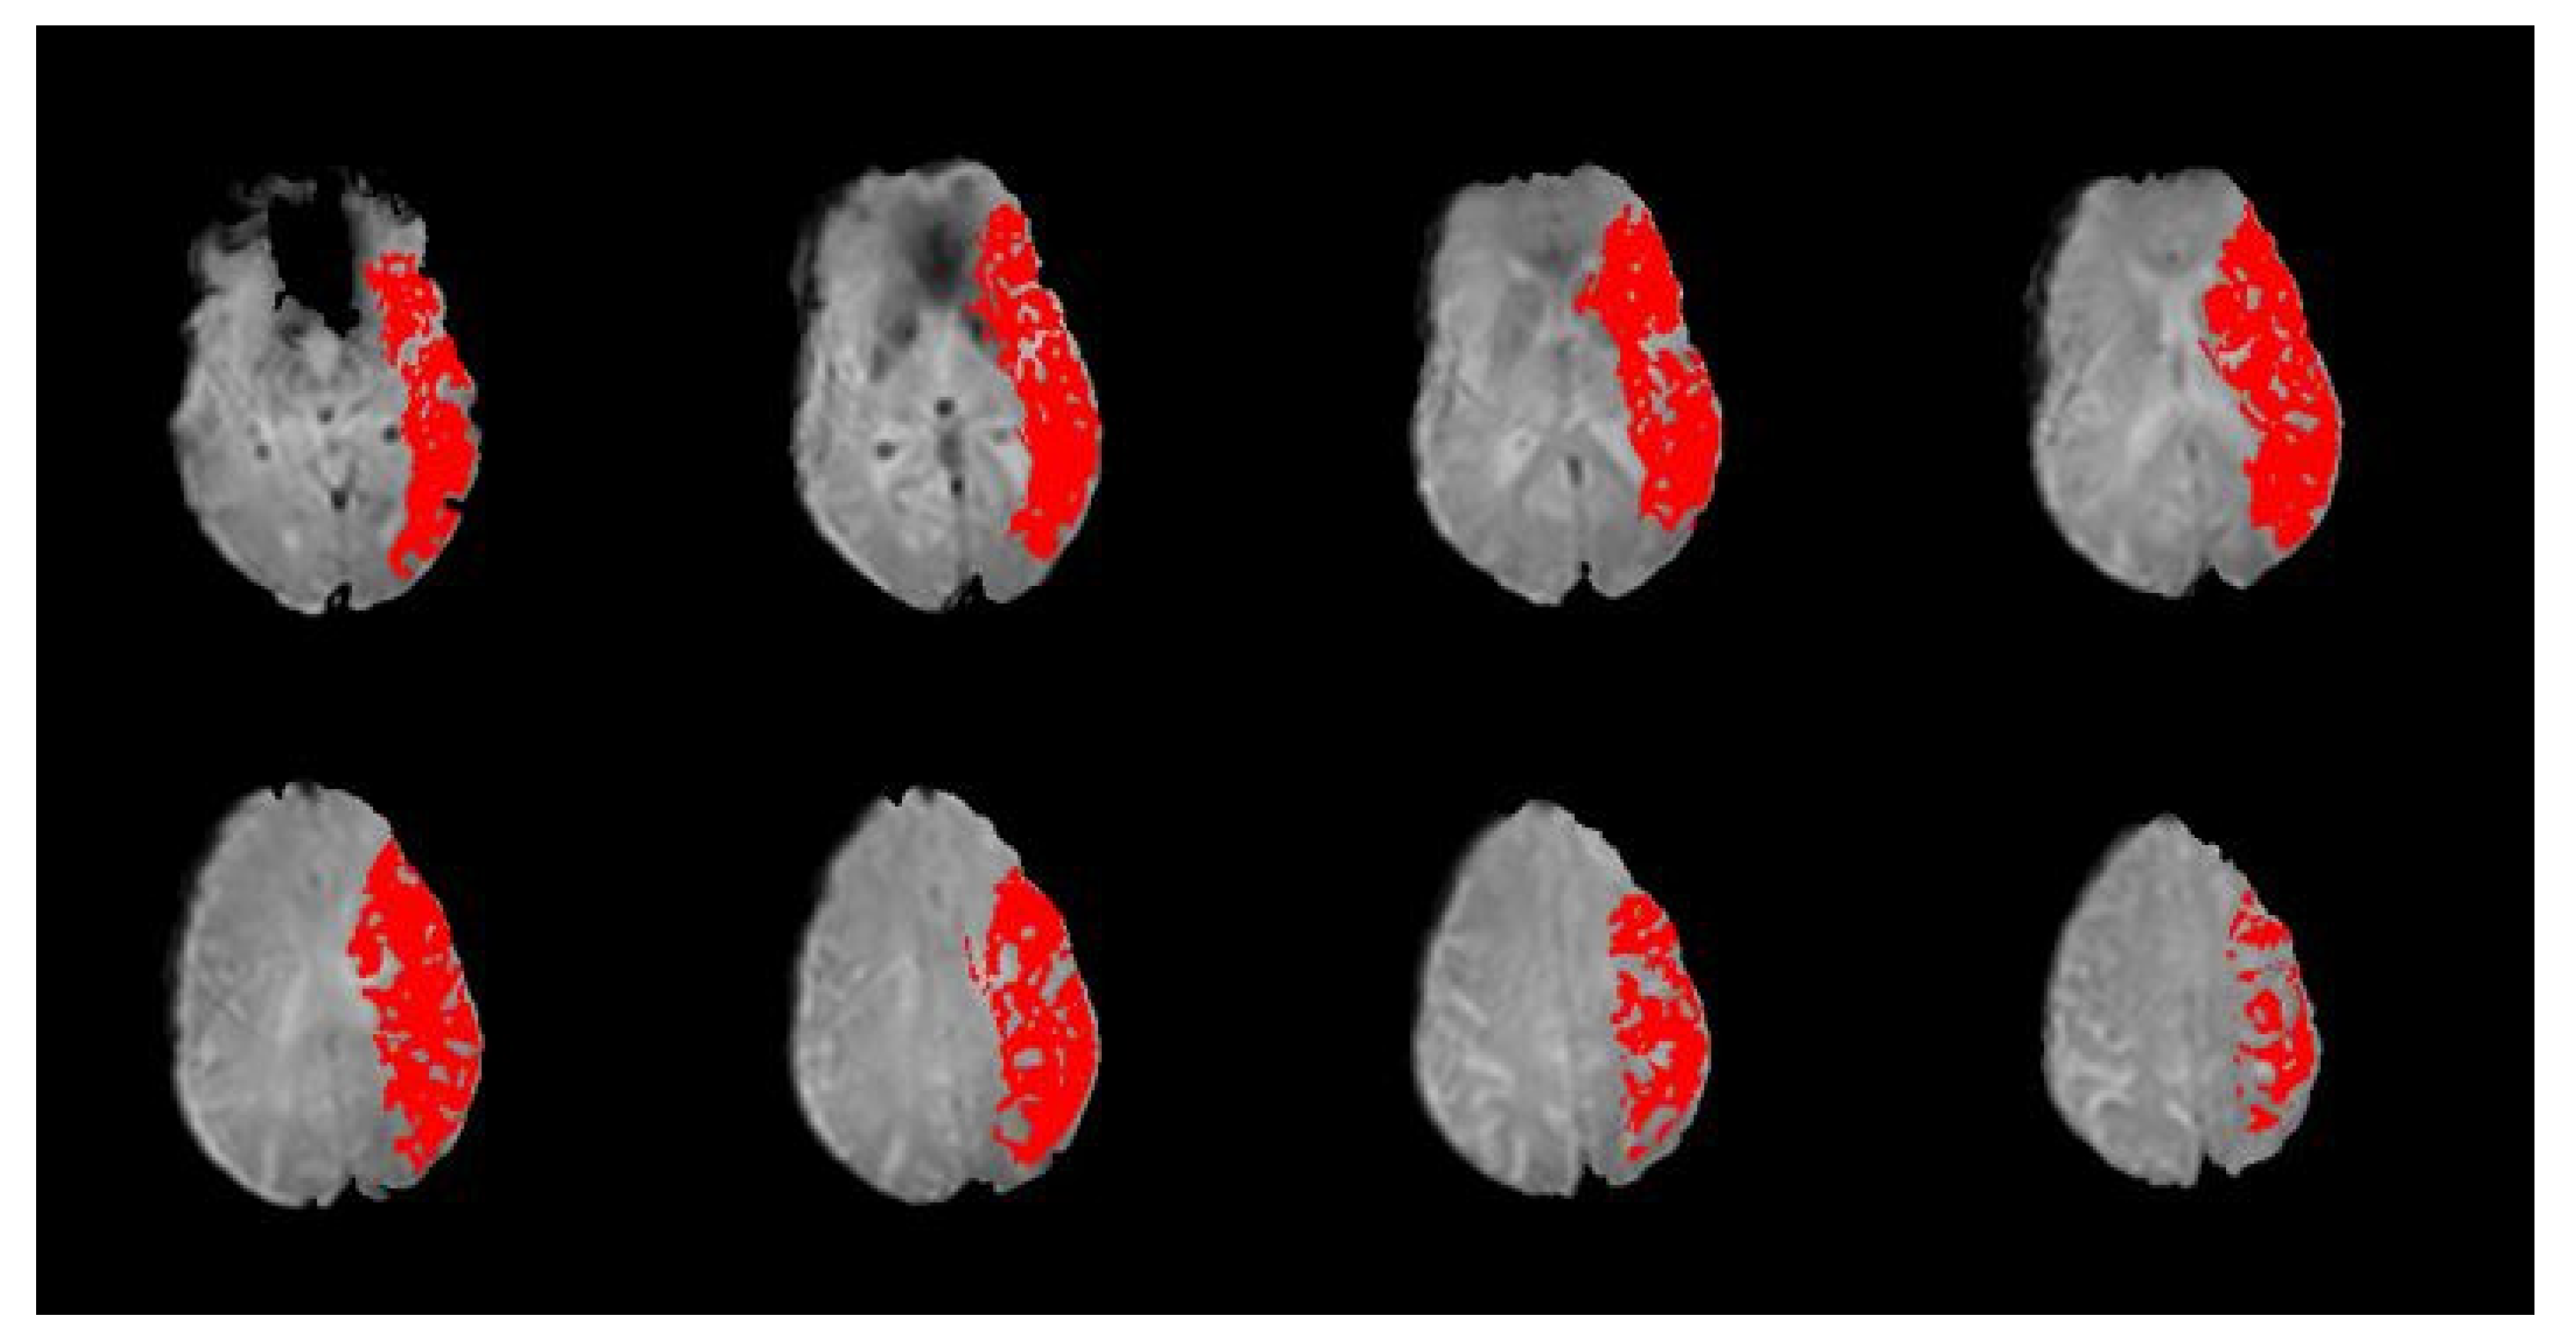

Time-to-peak (TTP) maps were created from PWI sequences by subtracting the TTP (i.e., time until maximal contrast concentration) for each voxel of normal tissue in the contralesional hemisphere from corresponding voxels in the ipsilesional hemisphere. A perfusion deficit was defined as a greater than 4-s delay in the TTP. TTP maps were created by an NIH investigator, and then de-identified before being shared for this study. An example is provided in Figure 2. For this analysis, while blinded to the NIH-FHV score, perfusion deficit was coded as present or absent in each of the six vascular regions as described previously (viz., ACA, PCA, MCA-F, MCA-T, MCA-P, and MCA-I).

Figure 2.

Sample slices from a participant’s PWI scan with time-to-peak (TTP) map overlay. A TTP delay of ≥4 s is shown in red. Per the slices included here, this participant would be coded as having a perfusion deficit present in all four regions of the MCA territory (frontal (MCA-F), temporal (MCA-T), parietal (MCA-P), and insular (MCA-I)).